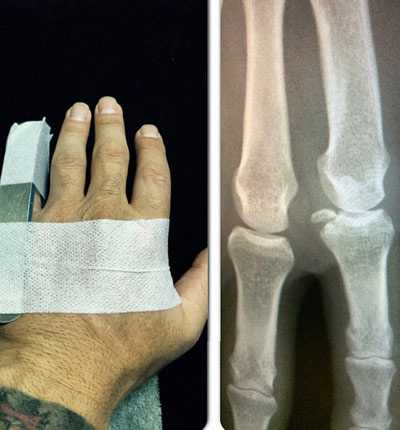

Necati Ateş: Hazırlık maçında görünmez kaza... İbrahim Dağaşan kardeşim parmaktan ufak bir parça aldı.